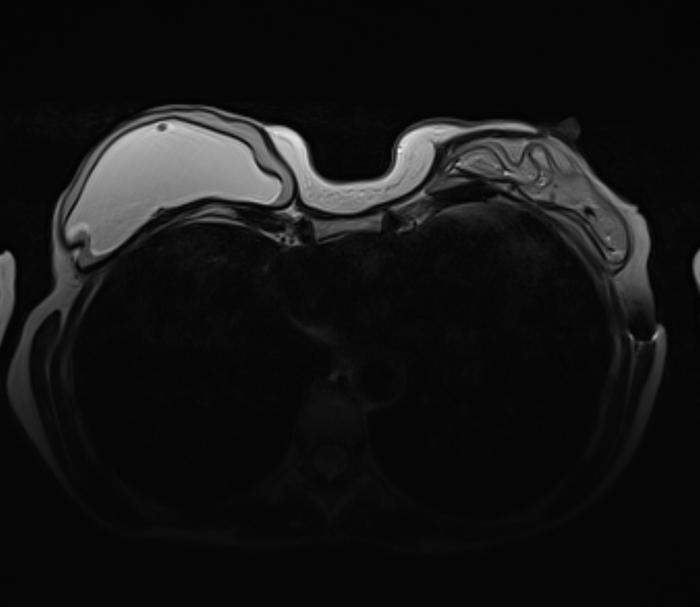

Пациентка, 64 года, перенесла двустороннюю мастэктомию (удаление обеих молочных желёз) по поводу рака 14 лет назад с пластикой с обеих сторон двухкамерные имплантами. Сейчас клинически подозревают фиброз капсулы и возможно разрыв левого импланта. Для подтверждения диагноза провели МРТ молочных желёз (только нативную часть протокола, т.е. без в/в введения контрастного вещества, от которого пациентка отказалась).

Начнём с краткого обзора здорового импланта:

Т2-взвешенное изображение

где центрально расположена камера, заполненная физ.раствором (голубой цвет), на периферии - камера, заполненная силиконом (красный цвет), и отграничено это всё фиброзной капсулой, которой тело старается отграничить инородный объект (пунктирная линия):

если мы сравним правый имплант с левым, то разница очевидна, тут не надо быть рентгенологом, чтобы понять что что-то тут не то, а именно сам имплант меньше, интенсивность сигнала иная (цвет более тёмный) + видны какие-то линии внутри импланта (красные стрелочки):

Линии эти - так называемый признак "лингвини" (или по-английски linguine sign), т.к. похожи они на одноимённую итальянскую пасту лингвини:

и являются ни чем иным как спавшимися стенками камер имплантов, что указывает на внутрикапсульный (в пределах образовашейся фиброзной капсулы) разрыв импланта, но без свободного выхода содержимого в окружающие мягкие ткани.

Интенсивность сигнала поменялась из-за того, что физ.раствор частично смешался с силиконом, и вследствие этого определяются пузырьки физ.раствора в силиконе - т.н. признак "салатного масла" или "salad oil sign" (капли, как при добавлении масла в воду):

которые я отметил красными стрелочками:

и на секвенции с подавлением воды, которая становится на картинке "чёрной" (синяя звёздочка), а силикон остаётся "белым" (красная звёздочка):

Имплант, соответственно, больше не жизнеспособен и его следует заменить.